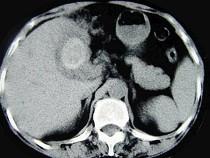

问题 女,55岁,右上腹痛多年,CT检查如图,最可能的诊断是 ( )

选项 A.胆囊胆固醇结石 B.胆囊胆红素结石 C.胆囊混合性结石并胆囊炎 D.胆囊癌 E.胆囊壁环状钙化

答案 C